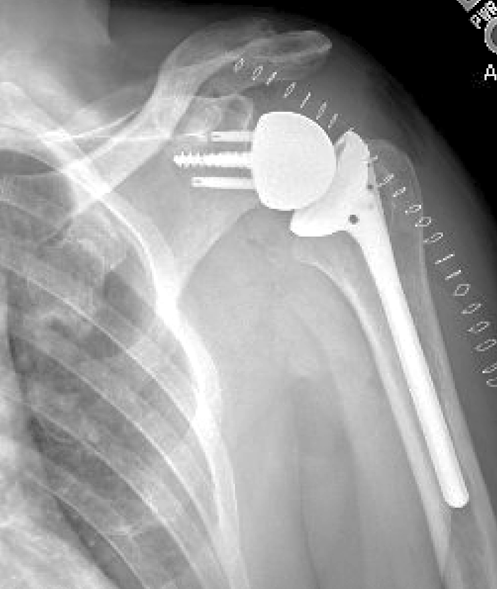

Deep learning to automatically classify very large sets of preoperative and postoperative shoulder arthroplasty radiographs had the goal of avoiding the laborious process of (1) manually observing and recording imaging information and (2 the lack of standard methods for transferring this information to a registry. The authors used a cohort of 2303 shoulder radiographs from 1724 shoulder arthroplasty patients. Two observers did a huge amount of manual work in labeling each radiograph according to (1) laterality (left or right), (2) projection (anteroposterior, axillary, or lateral), and (3) whether the radiograph was a preoperative radiograph or showed an anatomic total shoulder arthroplasty or a reverse shoulder arthroplasty.

The trained algorithm perfectly classified laterality and almost perfectly classified the imaging projection and the implant type. It took the algorithm 20.3 seconds to analyze 502 images. The authors also identified the features that the model used to predict the correct label for each task (see green dots used to predict prosthesis type).

Automated Shoulder Implant Manufacturer Detection using Encoder Decoder based Classifier from X-ray Images proposed an encoder-decoder based classifier along with the supervised contrastive loss function that can identify the implant manu- facturer effectively with accuracy of 92% from X-ray images.

Implant identification will be an important component of arthroplasty outcome research.

As in the prior study, Artificial intelligence for automated identification of total shoulder arthroplasty implants sought to develop an automated deep learning algorithm to identify shoulder arthroplasty implants from 3060 plain radiographs of patients having total shoulder arthroplasty (22 different reverse TSA and anatomic TSA prostheses from 8 implant manufacturers). The algorithm classified implants at a mean speed of 0.079 seconds per image. The model discriminated among the implants with an accuracy of 97%, and sensitivities between 0.80 and 1.00 on an independent testing set.

Examples showing high intra-class variabilities and low inter-class variabilities. Examples showing (a) high intra-class variability of one manufacturer (Cofield) and (b) low inter-class variability. In (b), upper-left, upper-right, lower-left, and lower-right images show the cases of four manufacturers of Cofield, Depuy, Tornier, and Zimmer, respectively.